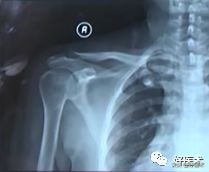

- X线照片:左侧:健侧;右侧:患侧术后

- 术后CT重建:肩锁关节对合略微欠佳,但该患者术后功能状态非常好